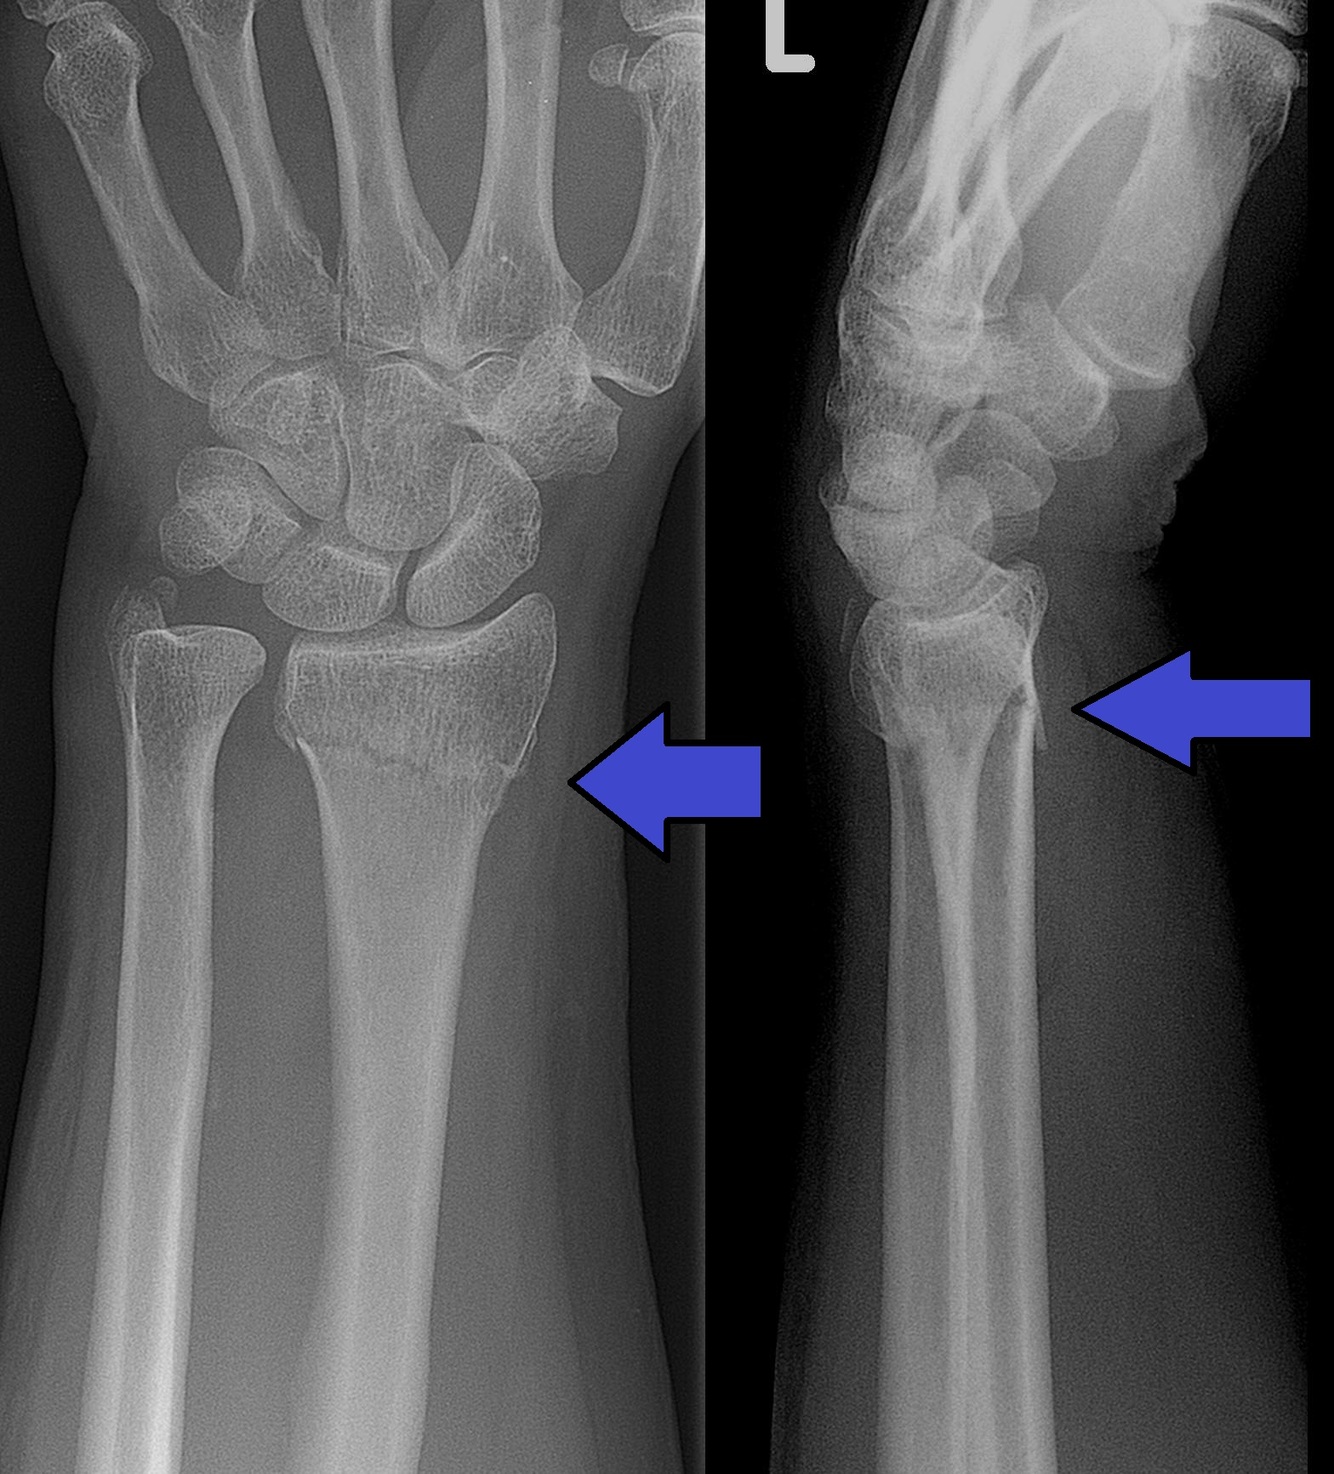

Which wrist fracture causes carpal tunnel syndrome

Colles fracture - complete fracture of distal radius causing dorsal displacement of radius